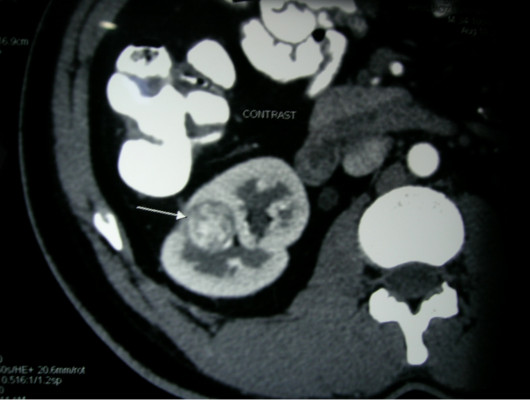

Large Kidney Tumour on CT Scan

• Physical exam for lumps. fever, high blood pressure.

• Urine and blood tests.

• Ultrasound scan , CT Scan, MRI.

• Renal arteriogram, Bone scan